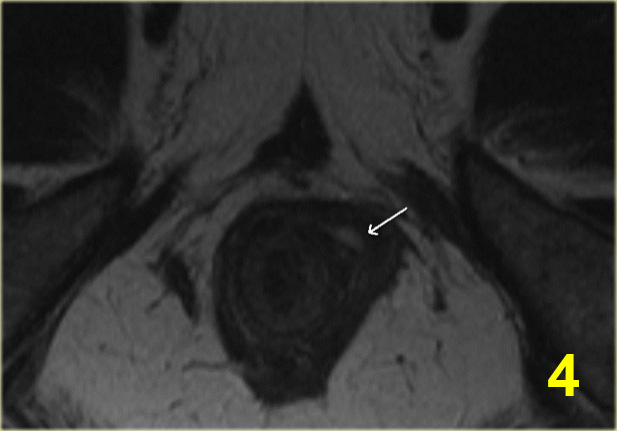

Bên trái là hình ảnh cắt ngang chuỗi xung T2W xóa mỡ của một đường rò xuyên cơ thắt với lỗ mở niêm mạc ở vị trí 11 giờ.